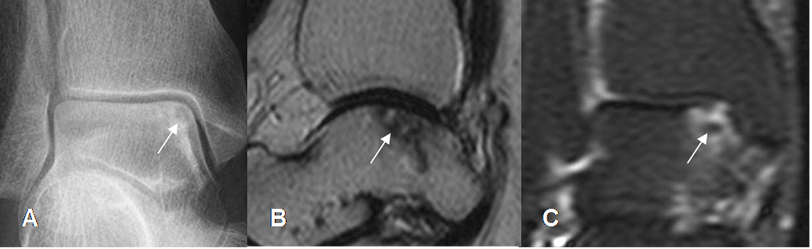

Fig 38. Lesión osteocondral.

A: Rx AP. Area radiolúcida en la parte superointerna del talo.

B: RM sagital en T2. Defecto hipointenso en la parte superior del talo, con algunas áreas hiperintensas.

C: RM coronal en STIR. Cambios inflamatorios en el talo, con zona hipointensa de necrosis.